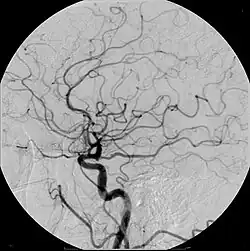

Meio de contraste, em diagnósticos por imagem, são substâncias administradas ao paciente com a finalidade de facilitar a distinção de estruturas anatômicas em seu estado normal ou patológico.

A depender da técnica de obtenção de imagens podem ser utilizadas diferentes substâncias. Mesmo a água pode ser considerada um meio de contraste quando, por exemplo, é utilizada para distender o estômago e duodeno na tomografia computadorizada (nessa ocasião considerada um contraste negativo). Meios de contraste podem ser administrados pelo trato gastrointestinal (via oral ou retal), via intravenosa, via intra-arterial, pelo trato genitourinário (ex.: vagina, útero ou uretra), ou ainda, durante procedimentos cirúrgicos, quando se deseja estudar estruturas profundas como a via biliar (colangiografia).

Quando administrado pela via intravenosa, é capaz de facilitar a identificação dos vasos sanguíneos, além de detectar alterações estruturais ou dinâmicas de funcionamento dos órgãos estudados, que em muitos casos, não seriam detectados de outra forma. Apesar de ter o potencial de alterar a função renal, na grande maioria das vezes o contraste iodado intravenoso o faz de maneira discreta e reversível, e por esse motivo, é amplamente utilizado pelo seu benefício, permitindo o diagnóstico e tratamento de condições de maior relevância para a saúde do paciente.